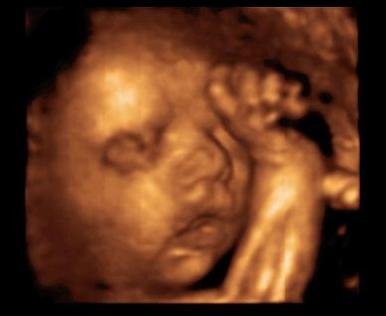

Ezen is a zsinór a sláger itt már puszilgatta :D Kép